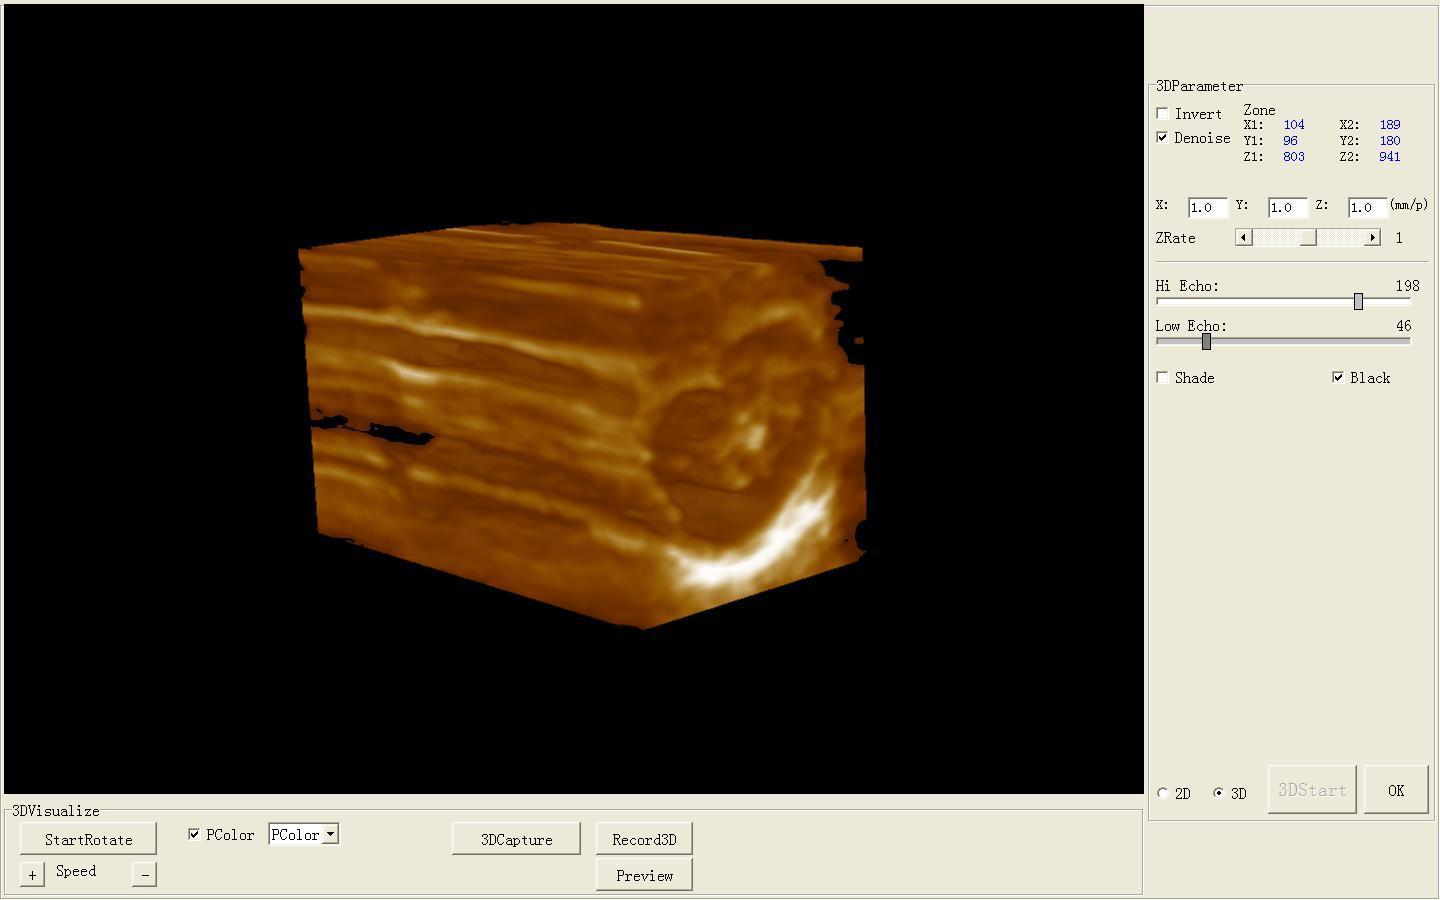

Full Digital Ultrasound Ultrasonic Scanner System 7.5 Mhz Linear Probe 3D image 190891058744

Model: RUS-9000B

software: NEW External 3D Software